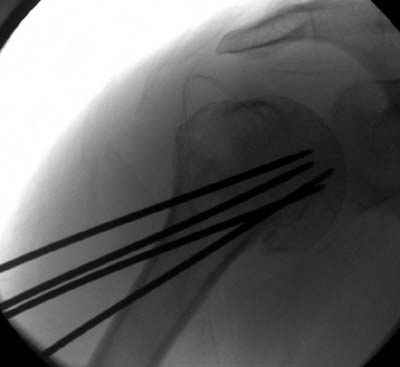

Пока я пользуюсь методикой принятой у нас (методика Сиэтла), также перкутанный спицевой метод, только сцицы 2.8 мм с резбой на конце.

Здесь случай перелома-вывиха плеча, больному 56 лет, после "дважды" закрытой неудачной репозиции, опять же ургентно взяли в операционную, после полного общего обезболивания попытались сделать репозицию, и фиксацию провели спицами.

Больной находился в повязке, примерно напоминяющей косыночную, рекомендованы движения в локтевом суставе и маятниковые движения в плече, спицы удалены в три недели (были случаи миграции)

Больной амбулаторный, предупрежден на случай осложнения АВН головки.